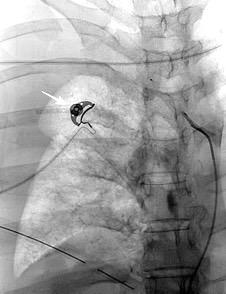

Quiste hidatídico.

Comunica con el hiato esofágico y el espacio pararrenal anterior.

Colecciones “inflamatorias” abdominales llegan al tórax vía el hiato esofágico o por vía transdiafragmática

Afectación transdiafragmática: 5,6-43,7% de quistes hepáticos. “Área desnuda” del hígado.

Panda A et al. “Straddling Across Boundaries”. Thoracoabdominal Lesions: Spectrum and Pattern Approach. Curr Probl Diagn Radiol. 2015 Área desnuda. El hígado en contacto directo con el tendón central del diafragma. Contiene el hiato de VCI.

Pedrosa I et al. Hydatid Disease: Radiologic and Pathologic Features and Complications. Radiographics 2000